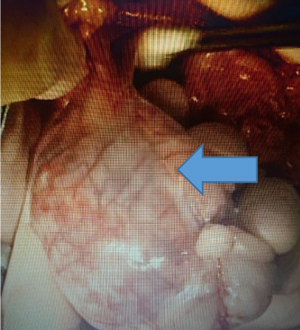

癌の進行状況によって治療は変わっていきます。

症状は時間が経つにつれて悪化していきます。以前は癌というと治療法はなく、亡くなってしまう病気と思われていました。しかし、獣医療の進歩により癌の中には完全に取り除いたり(根治治療)、生涯に渡ってコントロールすることで痛みや苦しみを和らげ(緩和療法)、生活の質(QOL)を保てたりする可能性が広がり、治療も日々変化しています。